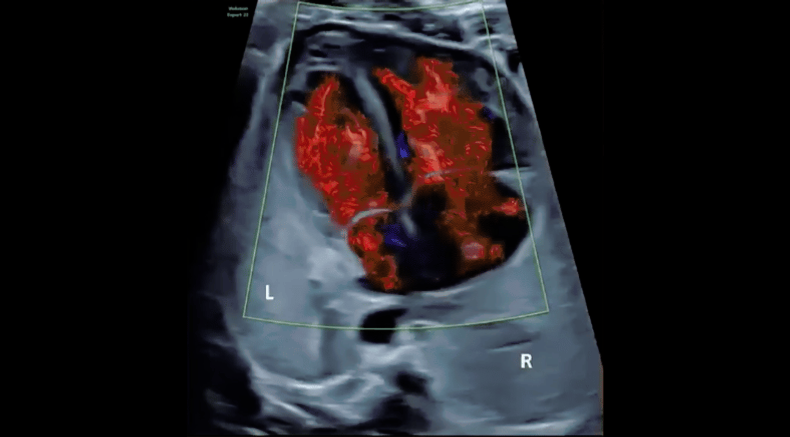

3D/4D rendering of intracardiac flow using spatiotemporal image correlation (STIC)

Chaoui, R. (2021), Evolution of fetal cardiac imaging in 30 years of ISUOG. Ultrasound Obstet Gynecol, 57: 38-42. https://doi.org/10.1002/uog.23551